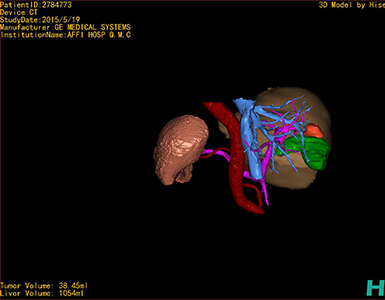

通过调节窗宽窗位调整CT序号,对肿瘤,肝实质,胆囊,下腔静脉,肿瘤,肝动脉、门静脉及肝静脉等进行三维重建;系统自动计算肿瘤体积和肝脏体积。

模拟手术操作,自动计算切除肿瘤体积。肝脏体积为1054ml,肿瘤体积为38.45ml,肿瘤体积为肝脏体积的3.6%,通过比对50-60岁正常肝脏体积为1330.41±329.13 ml,通过术前模拟手术,精准判断切除后剩余肝脏体积能耐受,避免肝衰竭发生。

术前三维重建:

重建图片